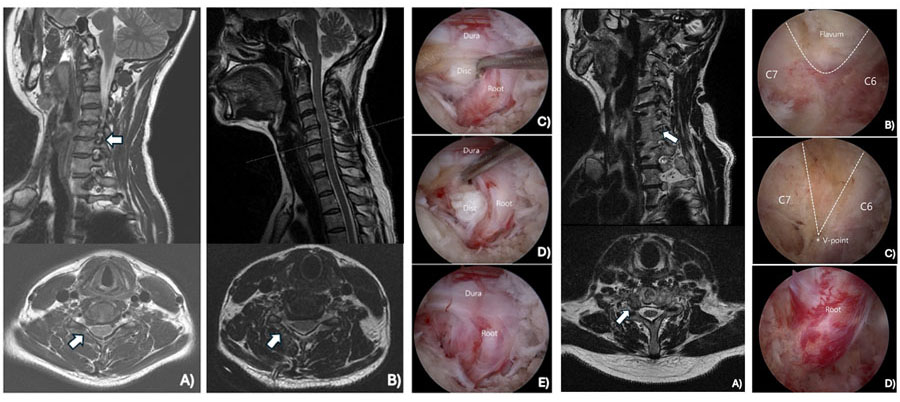

Recent interest has shifted toward motion-preserving surgical techniques, including cervical disc arthroplasty (CDA), endoscopic cervical spine surgery, laminectomy without fusion, and laminoplasty. Yet, evidence and best practices for these techniques in the context of DCM remain underexplored.

By Anson Bautista, Ivan Z. Liu, Ankit Mehta, Aditya Vedantam, C. Rory Goodwin, Nathan Evaniew, Paula Valerie ter Wengel ter Wengel, Daipayan Guha, Vafa Rahimi-Movaghar, Ryan Quisling, Jonathan Palmer, Keith Jackson, John DeVine, Jefferson R. Wilson, Uzondu F Agochukwu - Clinical Outcomes and Future Directions of Endoscopic Cervical Spine Surgery: A Systematic Review with Narrative Insights

By Ryan Wang, Satheeshram Tamilselvan, Ji Soo Ha, Aditya Vedantam, C. Rory Goodwin, Nathan Evaniew, Uzondu F Agochukwu, Konstantinos Margetis, Yoon Ha, Michael Fehlings, Jefferson R Wilson, Ankit Mehta - Cervical Laminectomy for degenerative cervical myelopathy: Is there a role in the modern day? A systematic review and meta-analysis